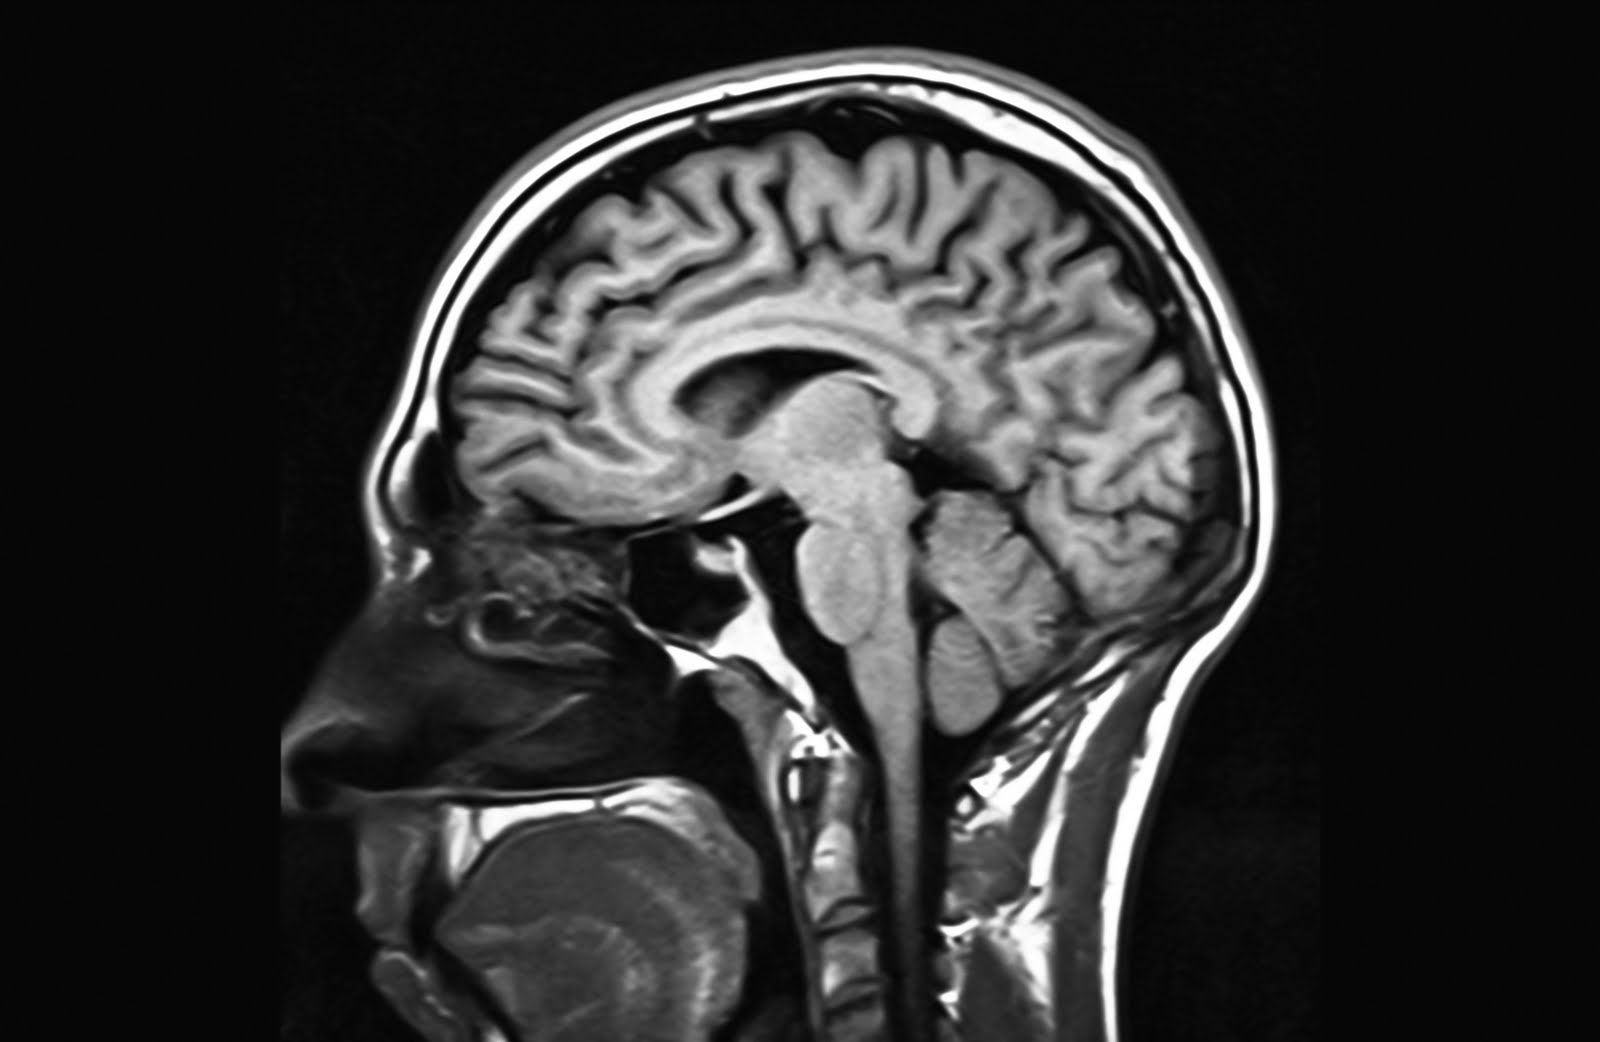

Sudden Sensorineural Hearing Loss Dr Sean Flanagan

From sydneyentclinic.com

Sudden Sensorineural Hearing Loss Dr Sean Flanagan Hearing Damage From Mri Learn how you can protect your hearing. overall, it seems that mri scanner noise does not pose a significant risk for permanent hearing loss as long as. magnetic resonance imaging (mri) devices produce noise, which may affect patient's or operators' hearing. our study, however, shows that sudden acute hearing loss was not significantly associated with an abnormal. Hearing Damage From Mri.

Sudden Sensorineural Hearing Loss Dr Sean Flanagan Hearing Damage From Mri standard clinical protocols require hearing protection during magnetic resonance imaging (mri) for patient. Learn how you can protect your hearing. did you know that the noise from an mri machine can cause hearing impairment and/or tinnitus? mr imaging implemented with a 3d flair sequence has provided new insights into the etiology of sudden sensorineural hearing. our. Hearing Damage From Mri.